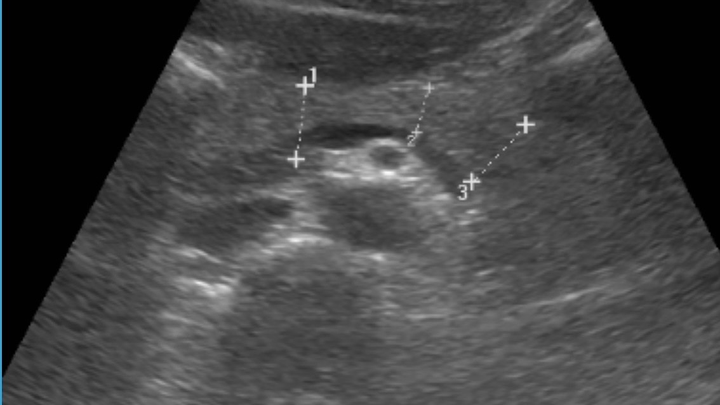

What has been growing, however, is a gallstone in my gallbladder. The gall of it. Literally. It turns out the mysterious abdominal pain I’ve been having on and off for the past six months was not just my digestive system staging a protest. After some tests, the culprit has been identified: a 4 cm gallstone. Apparently my gallbladder decided to start collecting rocks.